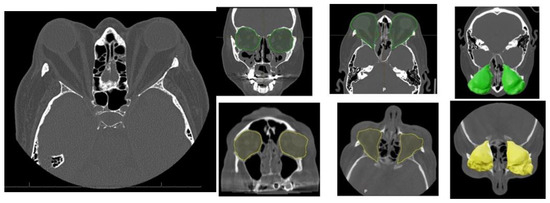

Orbital Computed Tomography (CT) imaging (Figure 2) revealed bilateral exophthalmos associated with substantial hypertrophy of intra- and extraconal orbital fat, alongside extraocular muscle enlargement. The superior recti muscles were primarily affected, with minor involvement of the right medial rectus and inferior recti muscles.

Figure 2.

Characteristic orbital findings in Graves’ orbitopathy. Axial and coronal CT images showing hallmark features of Graves’ orbitopathy, including bilateral enlargement of extraocular muscles (notably the inferior and medial rectus), with sparing of the tendinous insertions. Increased orbital fat volume and anterior displacement of the globe (proptosis) are also visible. These changes contribute to compressive effects on the optic nerve and are commonly used for diagnostic and preoperative planning purposes. Preoperative intra-orbital volume shown in green; postoperative volume in yellow.

Table 2 summarizes the orbital volume measurements obtained by computed tomography (CT) before and after surgical decompression in patients with Graves’ orbitopathy and compares them to established normative values. The mean normal orbital volume was 26.1 ± 3.3 cm3. In the affected orbits, preoperative volumes were already increased, averaging 30.1 cm3 in the right orbit and 30.3 cm3 in the left orbit. Following surgical decompression, the postoperative volumes further expanded to 33.6 cm3 and 34.3 cm3 in the right and left orbits, respectively. This corresponds to an average orbital volume increase of 3.5 cm3 in the right orbit and 4.0 cm3 in the left orbit.

Orbital volumetric analysis was conducted using preoperative and postoperative CT scans, selecting axial orbital images for evaluation. BrainLab software facilitated orbital volume quantification, demonstrating a significant increase postoperatively (Table 2). These volume changes correlated with proptosis reduction and intraocular pressure normalization, underscoring the efficacy of orbital decompression. Postoperative outcomes demonstrated notable improvement in proptosis, eyelid position, and ocular motility, along with enhanced orbital contour and overall facial aesthetics (Figure 5).